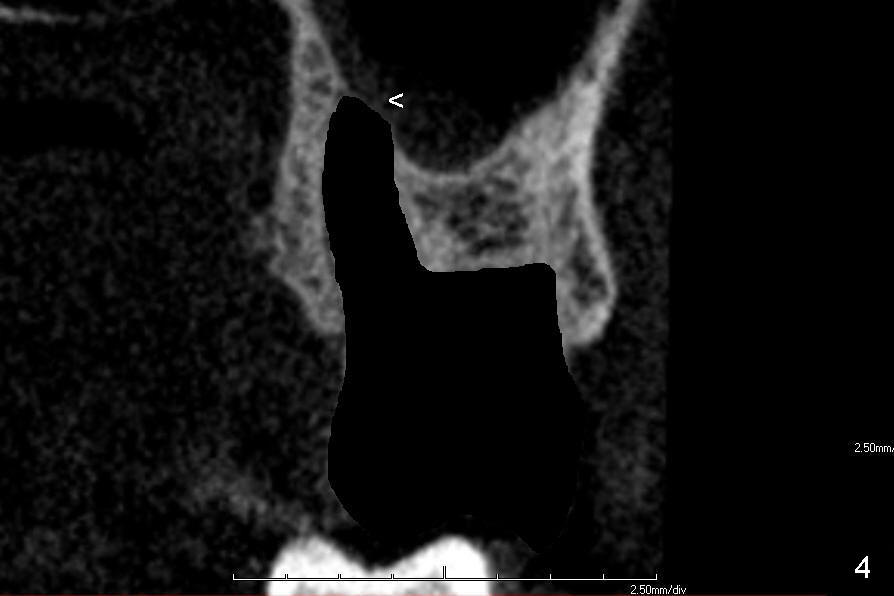

One of these two teeth is to be extracted first (Fig.4). Granulation tissue is removed, followed by copious irrigation. The socket morphology is studied. The apicobuccal aspect of the palatal socket is so thin that it may be perforated during tooth extraction and/or bone expansion mentioned below (Fig.4 <). Clindamycin gauze is placed in the extraction socket while the other tooth is being extracted.